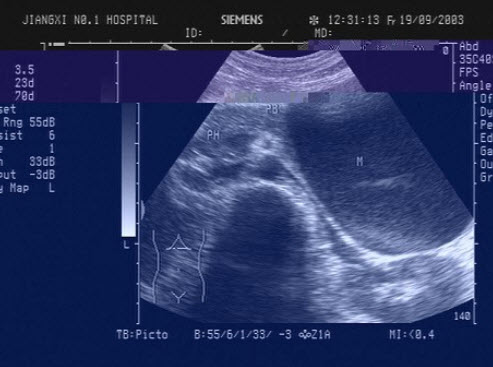

30、单项选择题

该病例最有可能诊断()

A.肺静脉畸形引流

B.上腔静脉型房缺

C.Ⅱ孔型房缺

D.卵圆孔重开

E.下腔静型房缺